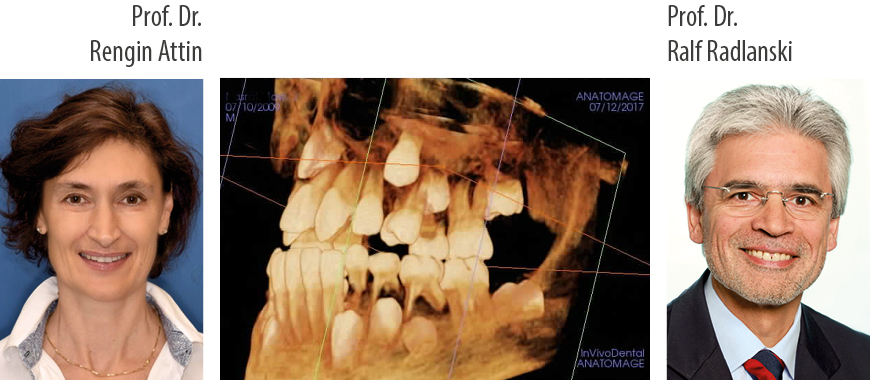

Online-Seminar:Prof. Dr. Rengin Attin & Prof. Dr. Dr. Ralf J. Radlanski: Kieferorthopädie im Milch- und Wechselgebiss und Initial-Läsionen

Kurzvita Prof. Dr. Rengin Attin:

Prof. Dr. Rengin Attin 1994 legte ihr Zahnmedizinisches Staatsexamen an der Universität Tübingen, Deutschland ab.

2001 absolvierte sie erfolgreich die Prüfung zur Spezialistin für Kinder- und Jugendzahnheilkunde, Deutsche Gesellschaft für Zahn-, Mund- und Kieferheilkunde (DGZMK).

In der Abteilung für Kieferorthopädie, Universität Göttingen erlangte Frau Attin 2004 den Fachzahnarzt für Kieferorthopädie. Seit 2007 bis heute ist sie als Kieferorthopädin in freier Praxis und an der Universität Zürich in der Klinik für Kieferorthopädie und Kinderzahnmedizin tätig.

Im Jahre 2010 erlangte sie die Venia Legendi im Fach Kieferorthopädie an der Universität Zürich.

Kurzvita Prof. Dr. Dr. Ralf J. Radlanski:

Prof. Dr. Dr. Ralf J. Radlanski (*1958), Studium der Medizin und Zahnmedizin in Göttingen und in Minneapolis (MN, USA). Wissenschaftlicher Assistent in den Abteilungen Morphologie und Embryologie des Zentrums Anatomie, Universität Göttingen, Ausbildung zum Kieferorthopäden an der Universität Göttingen. Habilitation 1989. 1992 Ernennung zum Professor und Direktor der Abteilung Orale Struktur- und Entwicklungsbiologie an der Freien Universität Berlin, Charité Univerisitätsmedizin Berlin. Gastprofessor an der University of California at San Francisco (USA), an der Universität Turku (Finnland), an der Universität Basel (CH). Kieferorthopädische teilzeit-Tätigkeit in freier Praxis in Berlin seit 1992. Präsident der EurAsian Association of Orthodontists (EAO), Wissenschaftlicher Berater des Berufsverbandes der Kieferorthopäden (BDK). Forschung auf dem Gebiet der Gesichtsentwicklung, der mikromorphologie orofacialer Strukturen und Beiträge zur praktischen Kieferorthopädie.

Mehr als 175 wissenschaftliche Publikationen, Autor (mit Karl Wesker) von „Das Gesicht, Bildatlas klinische Anatomie“, in 13 Sprachen, Autor von „Oral Structure And Biology (2018), Co-Autor der DVD-Reihe „Dynamics of Orthodontics“ (2000 – 2006), 15 Buchbeiträge, 60 betreute Dissertationen, über 300 eingeladene Vorträge und kieferorthopädische Fortbildungsveranstaltungen weltweit.

| Referent/en | Prof. Dr. Rengin Attin & Prof. Dr. Dr. Ralf J. Radlanski |